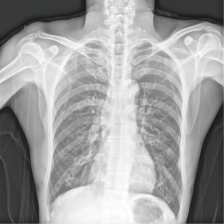

To pre-train a high-performance X-ray foundation model, the first thing we need to do is the collection of large-scale X-ray images. Therefore, a large-scale and high-resolution dataset that contains X-ray medical images is collected for the pre-training. Some representative samples are visualized in Fig. 3.